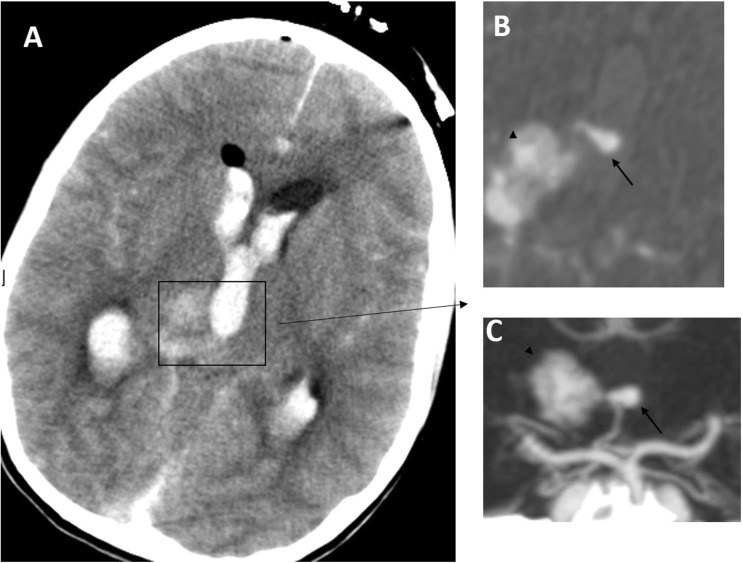

In common with others [7, 15], we advocate a multidisciplinary approach utilising multimodality treatment options including combining different treatment strategies to maximise the permanent nidus obliteration rate with low treatment morbidity. Our results and recent reports [7, 12, 15] add support to this concept. As an example, Fig. 4 demonstrates a right thalamic haemorrhage from an aneurysm on the artery of Percheron, in turn feeding the AVM. The patient presented with sudden onset headache and collapse with a GCS of 4/15; she had an emergency EVD followed by DSA and embolisation of the aneurysm and feeder using an ethylene vinyl alcohol copolymer (Onyx™) followed by radiosurgery with complete AVM/aneurysm obliteration (Fig. 5) and good recovery to mRS of 3. In centres where only a single or a combination of two treatment modalities is available, the number of patients in whom the treatment risks are deemed to exceed the calculated risks of natural history, and who therefore remain untreated, is comparatively high [13]. The availability of better neurosurgical/interventional facilities, including radiosurgery centres in the UK, has encouraged us and others to utilise more active and appropriate treatment strategies, yielding improved outcomes.

Fig. 4.

Case illustration. a Pre-treatment CT, which shows a right thalamic bleed with intraventricular extension and hydrocephalus after external drainage placement. b Axial CT angiogram image reveals the Percheron artery flow aneurysm projecting into the third ventricle (arrow) and AVM nidus (arrowhead). c A 3D CT angiogram picture that delineates the flow aneurysm (arrow) and the AVM nidus (arrowhead)